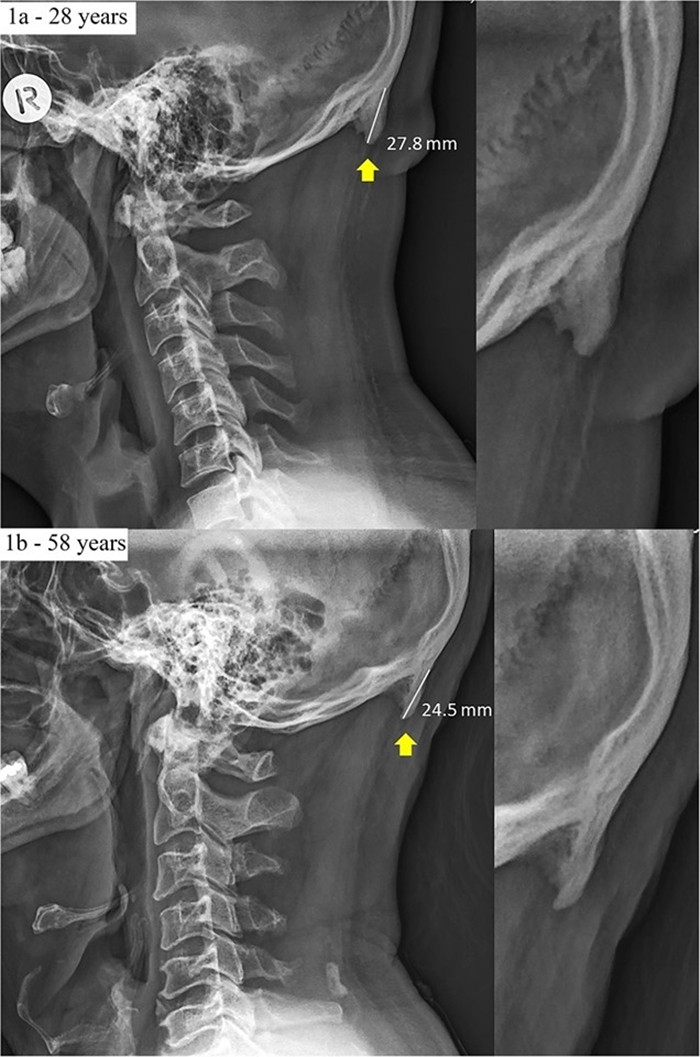

Trong phim X-quang đã ghi nhận một người 28 tuổi có khối u chẩm nhô ra ngoài hộp sọ 3mm so với một người 58 tuổi có cấu trúc xương bình thường. Các gai xương sọ - được biết đến như một phần nhô ra ngoài chẩm, đôi khi rất lớn, bạn có thể cảm nhận được nó bằng cách ấn ngón tay vào đáy hộp sọ. Tình trạng này có thể nghiêm trọng hơn ở những người thế hệ sau, khi có thói quen sử dụng smartphone từ khi còn nhỏ.

Trong các nghiên cứu, Shahar và đồng nghiệp đã xem xét ảnh chụp X-quang của nhiều bệnh nhân để tìm hiểu thêm về những xương gai này. Kết quả cho thấy, kích thước trung bình của xương gai trong khoảng 0,2 - 0,5 inch (0,5 - 1cm) trong đó có 10% xuất hiện những chiếc xương gai kích thước lớn từ 0,7 inch (2cm) trở lên. Chiếc xương gai lớn nhất được ghi nhân thuộc về một người đàn ông, dài 1,4 inch (3,57 cm).